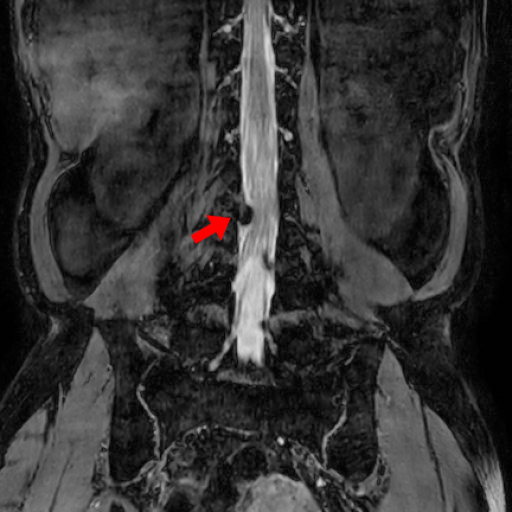

下記は私の腰のMRI画像です。

クリニックにデータが届く日に受診した結果は腰椎の椎間板ヘルニアでした。